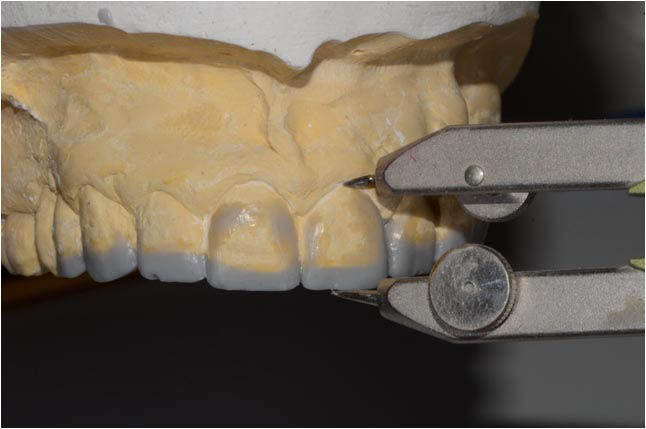

Diagnostic wax-up: the incisal margin is modified to mount the models in centric relation with the maximum intercuspation.

To achieve tooth elongation it is necessary to establish position, length, shape and size starting from the incisal edge of the two central incisors.